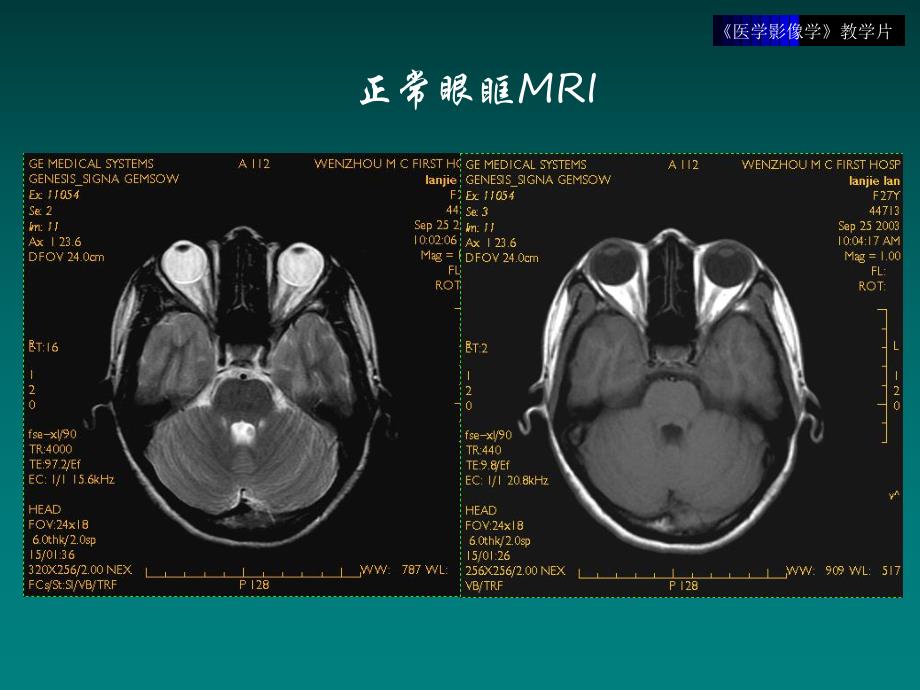

1、医学影像学教学片头颈部医学影像学教学片眼球医学影像学教学片正常眼眶MRI医学影像学教学片肿块型炎性假瘤医学影像学教学片肌炎型炎性假瘤医学影像学教学片弥漫炎症型炎性假瘤医学影像学教学片视网膜母细胞瘤医学影像学教学片视神经胶质瘤视神经胶质瘤医学影像学教学片眶内血管瘤医学影像学教学片眶内血管瘤医学影像学教学片眶内血管瘤增强:填充式强化医学影像学教学片Graves病医学影像学教学片眼眶骨折医学影像学教学片眼眶爆裂伤 医学影像学教学片眼眶内异物医学影像学教学片耳耳医学影像学教学片听小骨医学影像学教学片中耳炎医学影像学教学片慢性中耳炎医学影像学教学片胆脂瘤骨质破坏三维重建医学影像学教学片右侧乳突炎MRI医